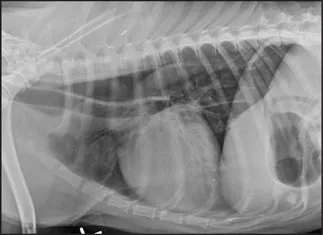

CASE 1.4 A 13-year-old spayed female mixed breed dog with a history of polyuria and polydipsia and abdominal distension. You obtain these thoracic radiographs: Fig. 1.4a, left lateral projection; Fig. 1.4b, dorsoventral projection.

1 What are your radiographic findings?

2 What is your radiographic diagnosis?

3 Are any additional radiographs needed?

Image

1.4a

1.4b